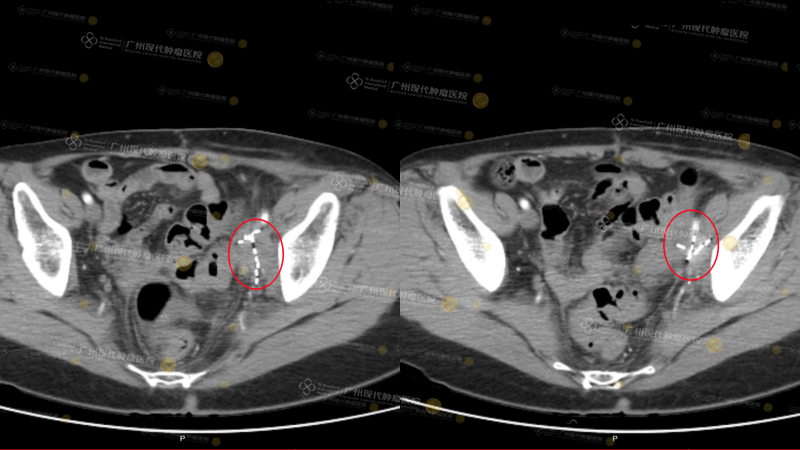

(Vùng chậu: sau 2 lần điều trị, khối u thu nhỏ 80%)(Phần tô sáng màu trắng là các hạt được cấy vào)